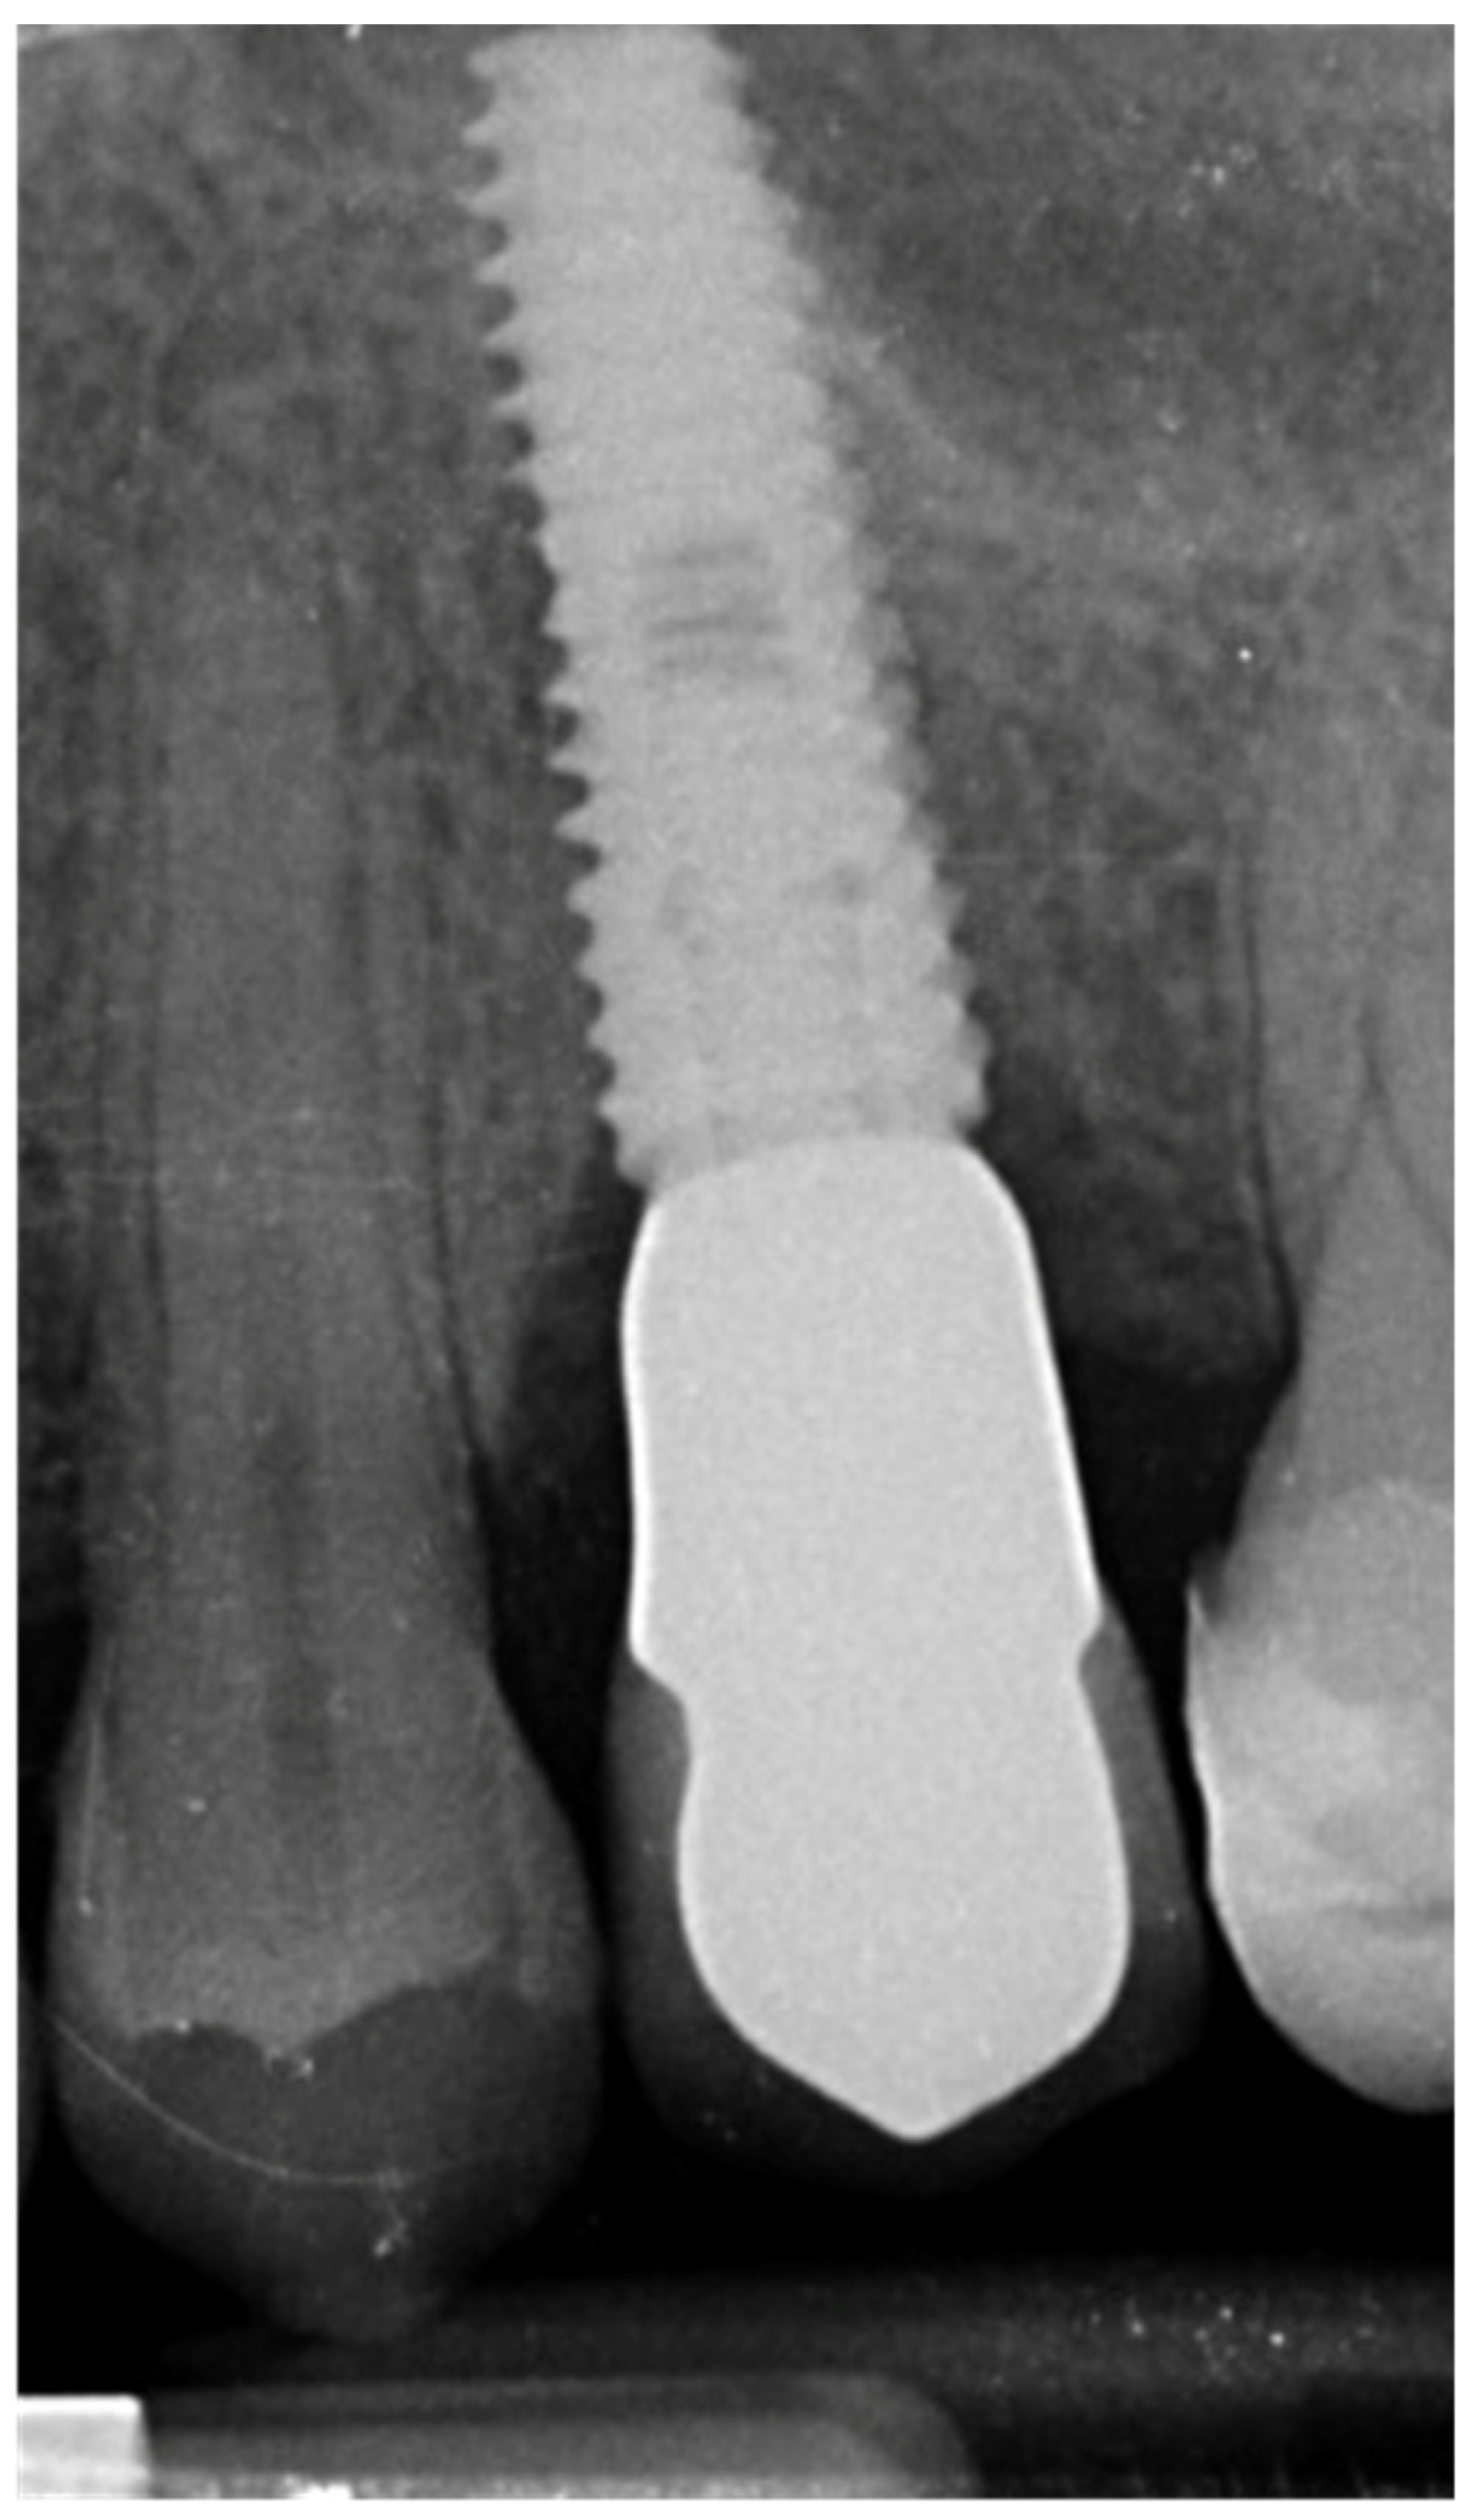

- Velásquez-Plata, D.; Lutonsky, J.; Oshida, Y.; Jones, R. A close-up look at an implant fracture: A case report. Int. J. Periodontics Restor. Dent. 2002, 22, 483–491. [Google Scholar]